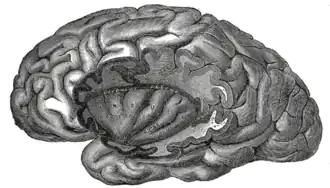

Die Inselrinde, auch Inselcortex, Cortex insularis, Lobus insularis, Insula, Insel, Reil-Insel oder Reilsche Insel (nach Johann Christian Reil, der sie 1796 erstmals beschrieb) genannt, ist ein Teil der Großhirnrinde. Zu jeder Hälfte des Großhirns (Telencephalon) gehört eine Insel; sie wird von den Opercula des Stirn-, Scheitel- und Schläfenlappens bedeckt.

In der pränatalen Entwicklung des Menschen ist das Größenwachstum der Insel geringer als das anderer Lappen des Großhirns, sodass deren Rindenanteile als Operculum frontale, Operculum frontoparietale und Operculum temporale die Insula überdecken. Infolge dieser Operkularisierung (Deckelung) liegt sie in der Tiefe des Sulcus lateralis, in der Fossa lateralis cerebri. Die Insel wird durch den Sulcus circularis von den Opercula abgegrenzt. Vom Inselpol strahlen fünf bis neun Windungen fächerförmig aus, der Sulcus centralis insulae teilt sie in einen vorderen Bereich mit den Gyri breves insulae und einen hinteren mit dem Gyrus longus insulae. Mit ihrem Limen insulae (Inselschwelle) genannten Pol grenzt sie an die paläokortikale Substantia perforata rostralis. Die Inselrinde selbst zählt zum Neocortex.